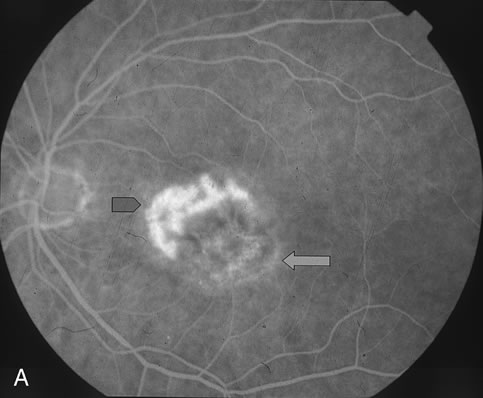

The classic and occult components of CNV are outlined in Figure 2. The percent of the CNV that is classic can then be determined as a proportion of the total CNV. In Figure 2A and B, the area of classic CNV measures 978 square microns and the total lesion measures 11,180 square microns. The classic component is thus 9% of the entire CNV and this lesion is classified as “minimally classic” CNV (defined as less than 50% classic CNV).23,40 The fluorescein angiogram demonstrates another mixed classic and occult CNV lesion in Figure 3. Using digital area measurements, the lesion in Figures 3A and B is composed of 79% classic CNV and fulfils the criteria for predominantly classic, subfoveal CNV that may benefit from verteporfin-PDT based on TAP findings.23,40 The TAP studies also demonstrated a visual benefit in eyes that had prior nonfoveal, thermal laser photocoagulation and subsequent recurrence of CNV below the fovea.23,40 In Figure 4A, subfoveal CNV recurrence in an eye with prior thermal photocoagulation is demonstrated. One month following verteporfin-PDT treatment, Figures 4B (early phase) and 4C (late phase) demonstrate characteristic hypofluorescence of the treated subfoveal CNV on fluorescein angiography.

Fig. 2. A. Fluorescein angiogram demonstrates minimally classic CNV. B. Digital imaging outlines the classic CNV component (A) and the entire lesion (classic and occult, marked as B). The area of classic component measures 978 square microns. The entire lesion measures 11,180 square microns.